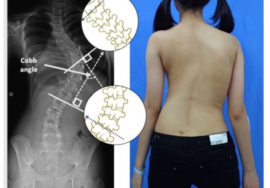

كيف يتابع الأطباء نجاح العلاج؟

يستخدم الأطباء زاوية كوب لقياس درجة الانحناء. وبعد كل جلسة تجبير، يطلب الطبيب صورة أشعة لتقييم التغيرات. وكلما انخفضت الزاوية تدريجيًا، دل ذلك على استجابة العمود الفقري للعلاج.